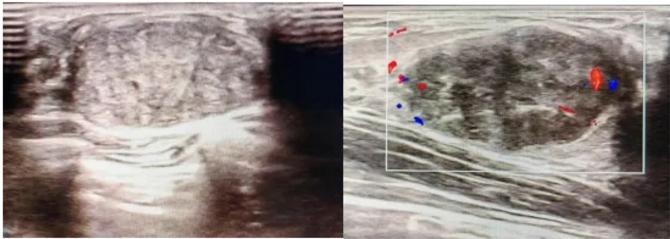

2.彩超報告關鍵指標

形態(tài):良性多呈橢圓形或分葉狀,邊界光滑。

縱橫比: 良性通常<1(橫徑>縱徑) 。

血流信號:纖維瘤血流較少,惡性常伴豐富雜亂血流。

鈣化:粗大鈣化多為良性,細小簇狀鈣化需警惕惡性。

BI-RADS分級:2-3類提示良性,4類以上需進一步檢查。

典型表現(xiàn):

橢圓形低回聲團塊,包膜完整,內部回聲均勻,后方回聲增強,周邊無“蟹足樣”浸潤。